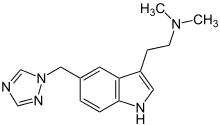

| Rizatriptan | artificial | 5-(CH2(N3(CH)2)) | CH3 | CH3 | N,N-dimethyl-2-[5-(1H-1,2,4-triazol-1-ylmethyl)-1H-indol-3-yl]ethanamine | 145202-66-0 |